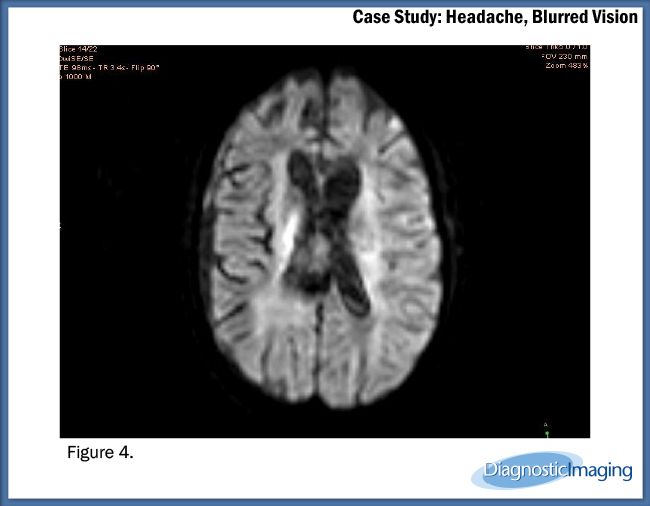

Case History: 20-year-old female with severe headache, blurred vision, vomiting.

Case History: 20-year-old female presented with severe headache, blurred vision, and vomiting.